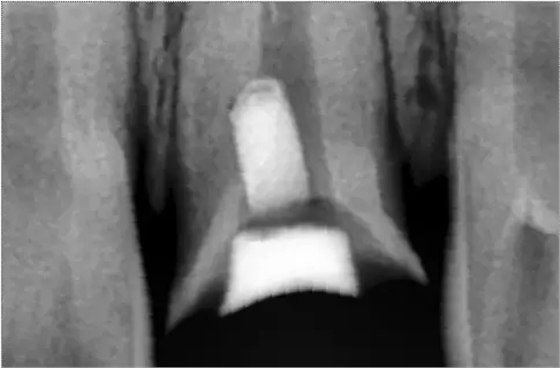

患者外院螺紋樁核加樹脂冠

X線片顯示螺紋釘出根管壁

MTA修補(bǔ)后的X片